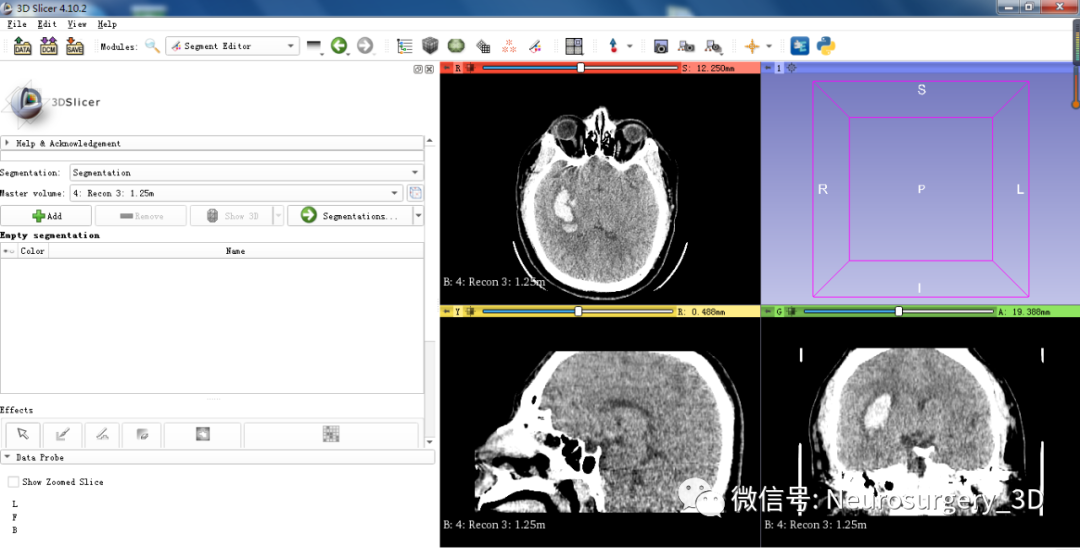

3、数据导入成功后,点击工具界面segment editor

4、应用阈值分割法三维重建血肿